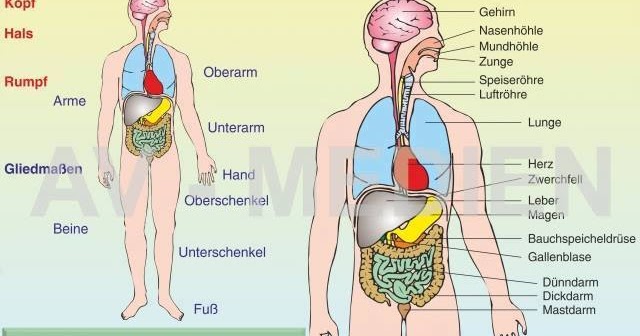

-n.+das+Ohr" width="550" alt="Tief in ihren Körper" title="Tief in ihren Körper">-en.+der+Mund.+die+Nase.+der+Hals..jpg" width="550" alt="Tief in ihren Körper" title="Tief in ihren Körper">